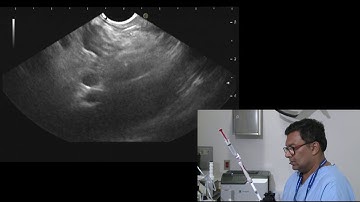

Having a lymph node biopsy